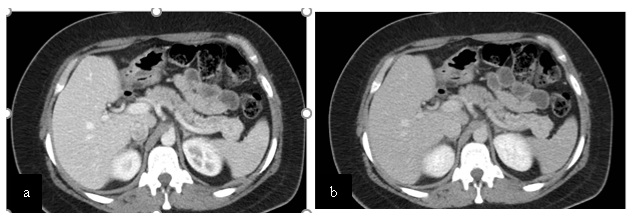

Paciente femenina de 48 años de edad que ingresa a Hospital Sanatorio Franchin por síntomas de cefalea y mareos, cuadro que se hace progresivo, presentando síncopes y posteriormente alteración del estado de conciencia. Los exámenes clínicos revelan una glucosa de 40 mg/dl, concomitante con insulina alta y péptido C elevado. Ingresa de forma programada para realización de duodeno pancreatectomía el 29 de mayo de 2021. Imágenes diagnósticas muestran estudio trifásico de tomografía de abdomen, lesión nodular en la cabeza del páncreas con ávido realce en fase arterial que en resonancia magnética se observa hiperintensa en T2, presenta restricción con la difusión y caída de la señal en el ADC. Además presenta realce tras la administración de contraste con gadolinio.

Ahora bien, como se mencionaba al principio, el estudio ecográfico es de muy baja sensibilidad y se identifique o no la lesión por este estudio, nuestro siguiente paso en el algoritmo diagnóstico de esta lesión es la tomografía. Esta es la prueba no invasiva inicial, con una sensibilidad del 63% al 83%, y detecta del 70% al 80% de los tumores. Esta debe realizarse como un estudio trifásico: fase arterial temprana a los 30 segundos, fase venosa a los 70 segundos, fase tardía de 3 a 5 minutos. La característica de estos tumores por tomografía es que se presentan como una masa sólida que tiene un ávido realce en la fase arterial, cuyo realce se mantiene y se observa más tenue en la fase venosa y en los tiempos tardíos la lesión se homogeniza.

La resonancia magnética es el otro estudio de imagen no invasivo que nos permite la detección de la lesión con una sensibilidad mayor que la de la tomografía, del 85% al 95%, donde los insulinomas presentan un realce tras la administración de contraste con gadolinio y secuencias T1 sin contraste son lesiones hipointensas y en secuencias T2 son hiperintensas.

Para mi caso, y dando una visión general de los métodos de imagen no invasivos en esta revisión retrospectiva, solo a uno de los pacientes se le detectó la lesión por ecografía, donde se visualizó una lesión nodular hipoecogénica en el cuerpo del páncreas. A los demás pacientes se les detectó la lesión por tomografía en estudio trifásico, donde resaltan las características ya descritas por la literatura de lesiones hipervasculares con intenso realce en fase arterial, localizadas en diferentes partes del páncreas, como cabeza, cuerpo y cola.

La resonancia magnética confirmó aún más el diagnóstico de las lesiones ya previamente visualizadas en tomografía en esta revisión, con realce de las lesiones en secuencias T1 y contraste con gadolinio, y en las secuencias funcionales con restricción de la lesión y caída de la señal en el mapa de ADC.